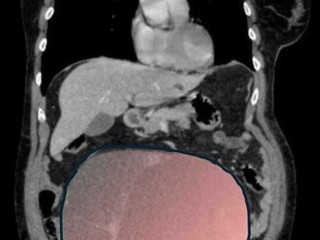

Per mesi la gigantesca cisti ovarica, con un diametro di circa 28 centimetri, è rimasta nascosta, senza dare segnali evidenti. La paziente non si era accorta di nulla. L’allarme è scattato quando la massa, associata alla presenza di una seconda neoplasia intestinale, ha iniziato a comprimere il colon, provocando sintomi acuti ed improvvisi fino ad una grave difficoltà intestinale non più ignorabile.

Fondamentale in questa fase il contributo della Radiologia dell'ospedale Sant’Anna, che fornisce l’imaging preoperatorio indispensabile per affrontare un quadro clinico di eccezionale complessità.

Durante l’intervento emerge tutta la gravità della situazione. La gigantesca neoplasia ovarica viene asportata: pesa circa 6 chilogrammi, con un volume paragonabile a quello di una gravidanza gemellare a termine. Ma non è l’unica minaccia. I sintomi più pericolosi sono legati alla sofferenza intestinale, che richiede un intervento immediato e coordinato di più specialisti.